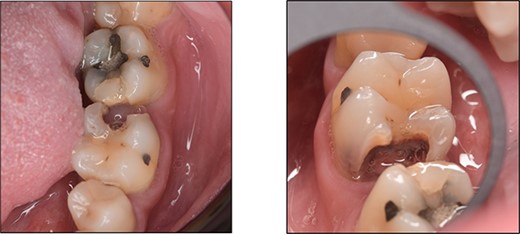

A 59-year-old male patient presented with a complaint of pain while biting on his lower left posterior teeth. Clinical examination revealed an extensive amalgam restoration on the lower left first molar (tooth 36) with a fractured restoration and secondary caries on the lingual aspect. The tooth was non-responsive to thermal testing and electrical pulp sensibility testing (EPT) and was tender to percussion. Radiographic examination showed radiolucency beneath the restoration on the mesial root surface, indicative of caries, along with furcation involvement and peri-radicular radiolucency. The tooth was diagnosed with pulpal necrosis and symptomatic apical periodontitis associated with extensive root caries (Fig. 6 and 7).

Clinical photograph of tooth 36 showing extensive amalgam restoration on mesio-occlusal-disto-bucco-lingual (MODBL).